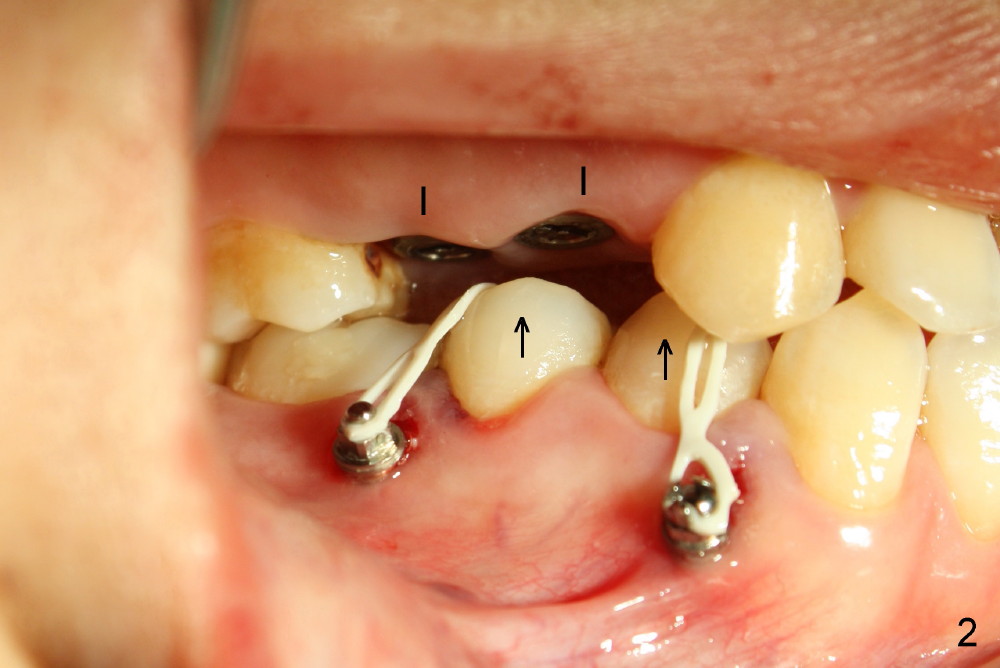

Twenty-seven-year-old Mickey has short clinical crowns in the maxilla (Fig.1). Two of the premolars (#4,5) have severe caries. When immediate implants were placed (Fig.2: I), there is no room to install abutments, probably due to the supraeruption of the opposing teeth (Fig.2 arrows). Three mini-implants (2 buccal (Fig.2), one lingual (Fig.3 <) were placed for intrusion.